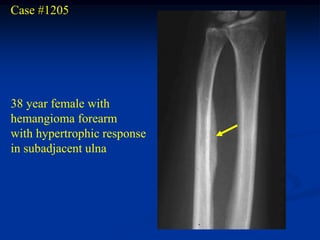

Case #1205

38 year female with

hemangioma forearm

with hypertrophic response

in subadjacent ulna

Bone scan

bone

hypertrophy

Axial PD MRI

Axial gad contrast MRI

Sagittal T-2 MRI

Case #1205 38 yearfemale with hemangioma forearm with hypertrophic response in subadjacent ulna